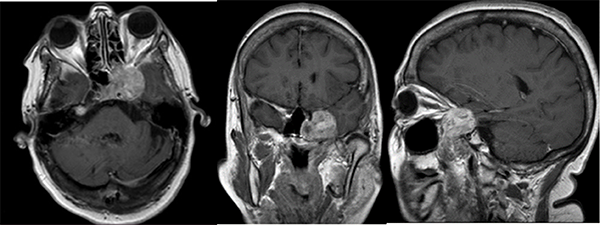

La resonancia magnética nuclear (RMN) evidenció una lesión a nivel del seno cavernoso izquierdo, la cual impresionaba proyectarse sobre el cavum, la fisura orbitaria y sector lateral izquierdo de la silla turca. Presentaba realce heterogéneo posterior a la inyección de contraste endovenoso, tenía un aspecto polilobulado y un diámetro máximo de 49x32x30 mm (CCxTxAP). (Fig 1.)

En base al cuadro clínico y los estudios complementarios, se decidió la resolución del cuadro por vía quirúrgica con presunto diagnóstico de un meningioma del seno cavernoso.